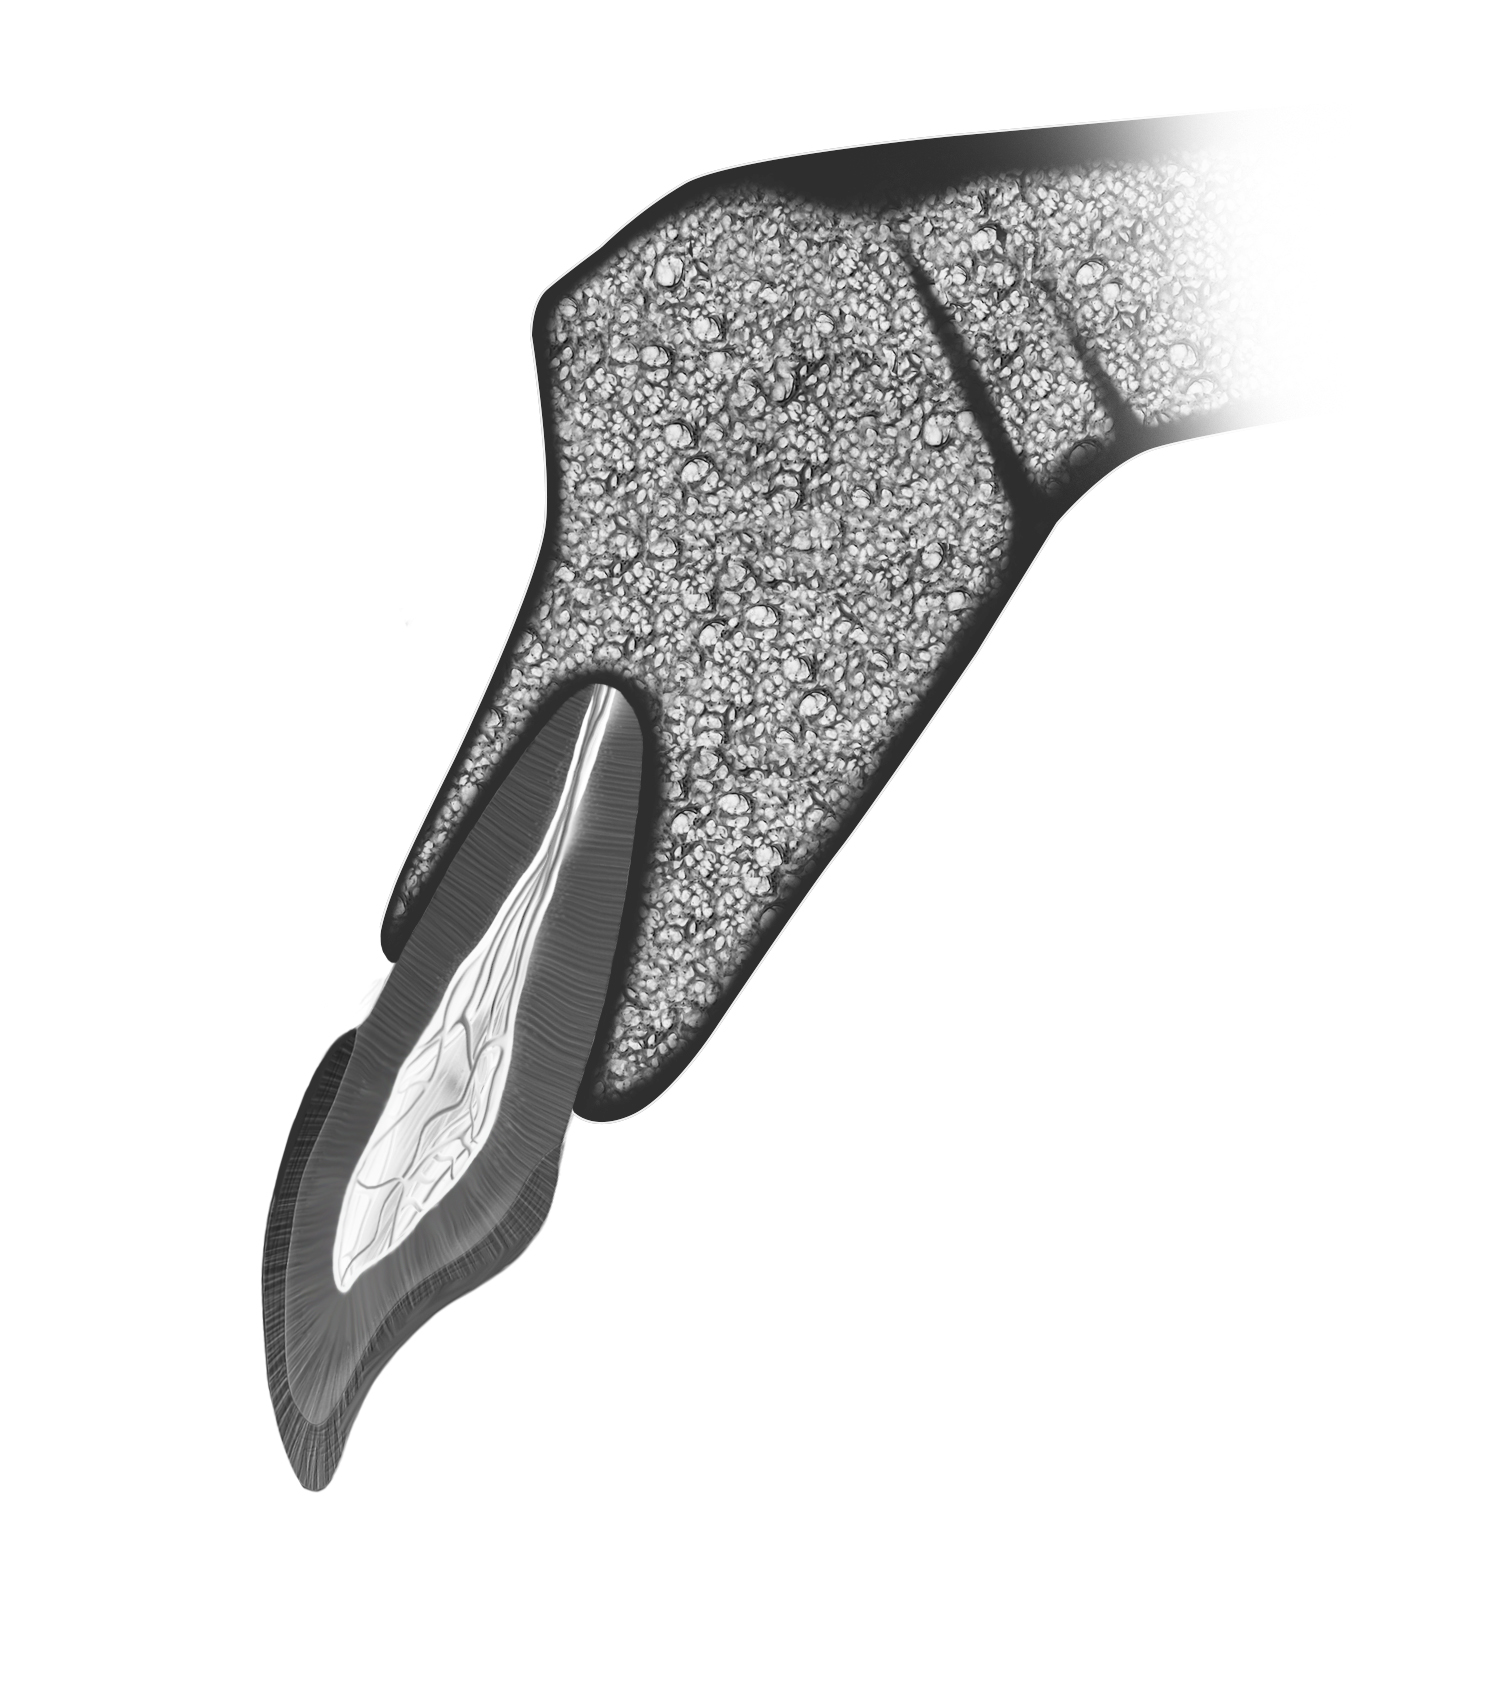

Kan et al9 showed that in 76% to 86.5% of cases, the tooth position in the anterior maxilla is most often positioned very close to the buccal plate (Figure 1). This plate and the roots are proclined forward from the nasal spine. Consequently, together with the crown–root angulation offset, a straight implant fixture is unlikely to be able to fully satisfy both root and crown positions, particularly if the prosthesis is to be screw retained.

Fig 1. The most common position of the tooth in the anterior maxilla, with the root in intimate contact with the buccal cortical plate. Note the biaxial relationship between the tooth crown and root.

Figure 1

Fig 3. Root-to-crown offset of 8 to 12 degrees for anterior teeth.

Figure 3